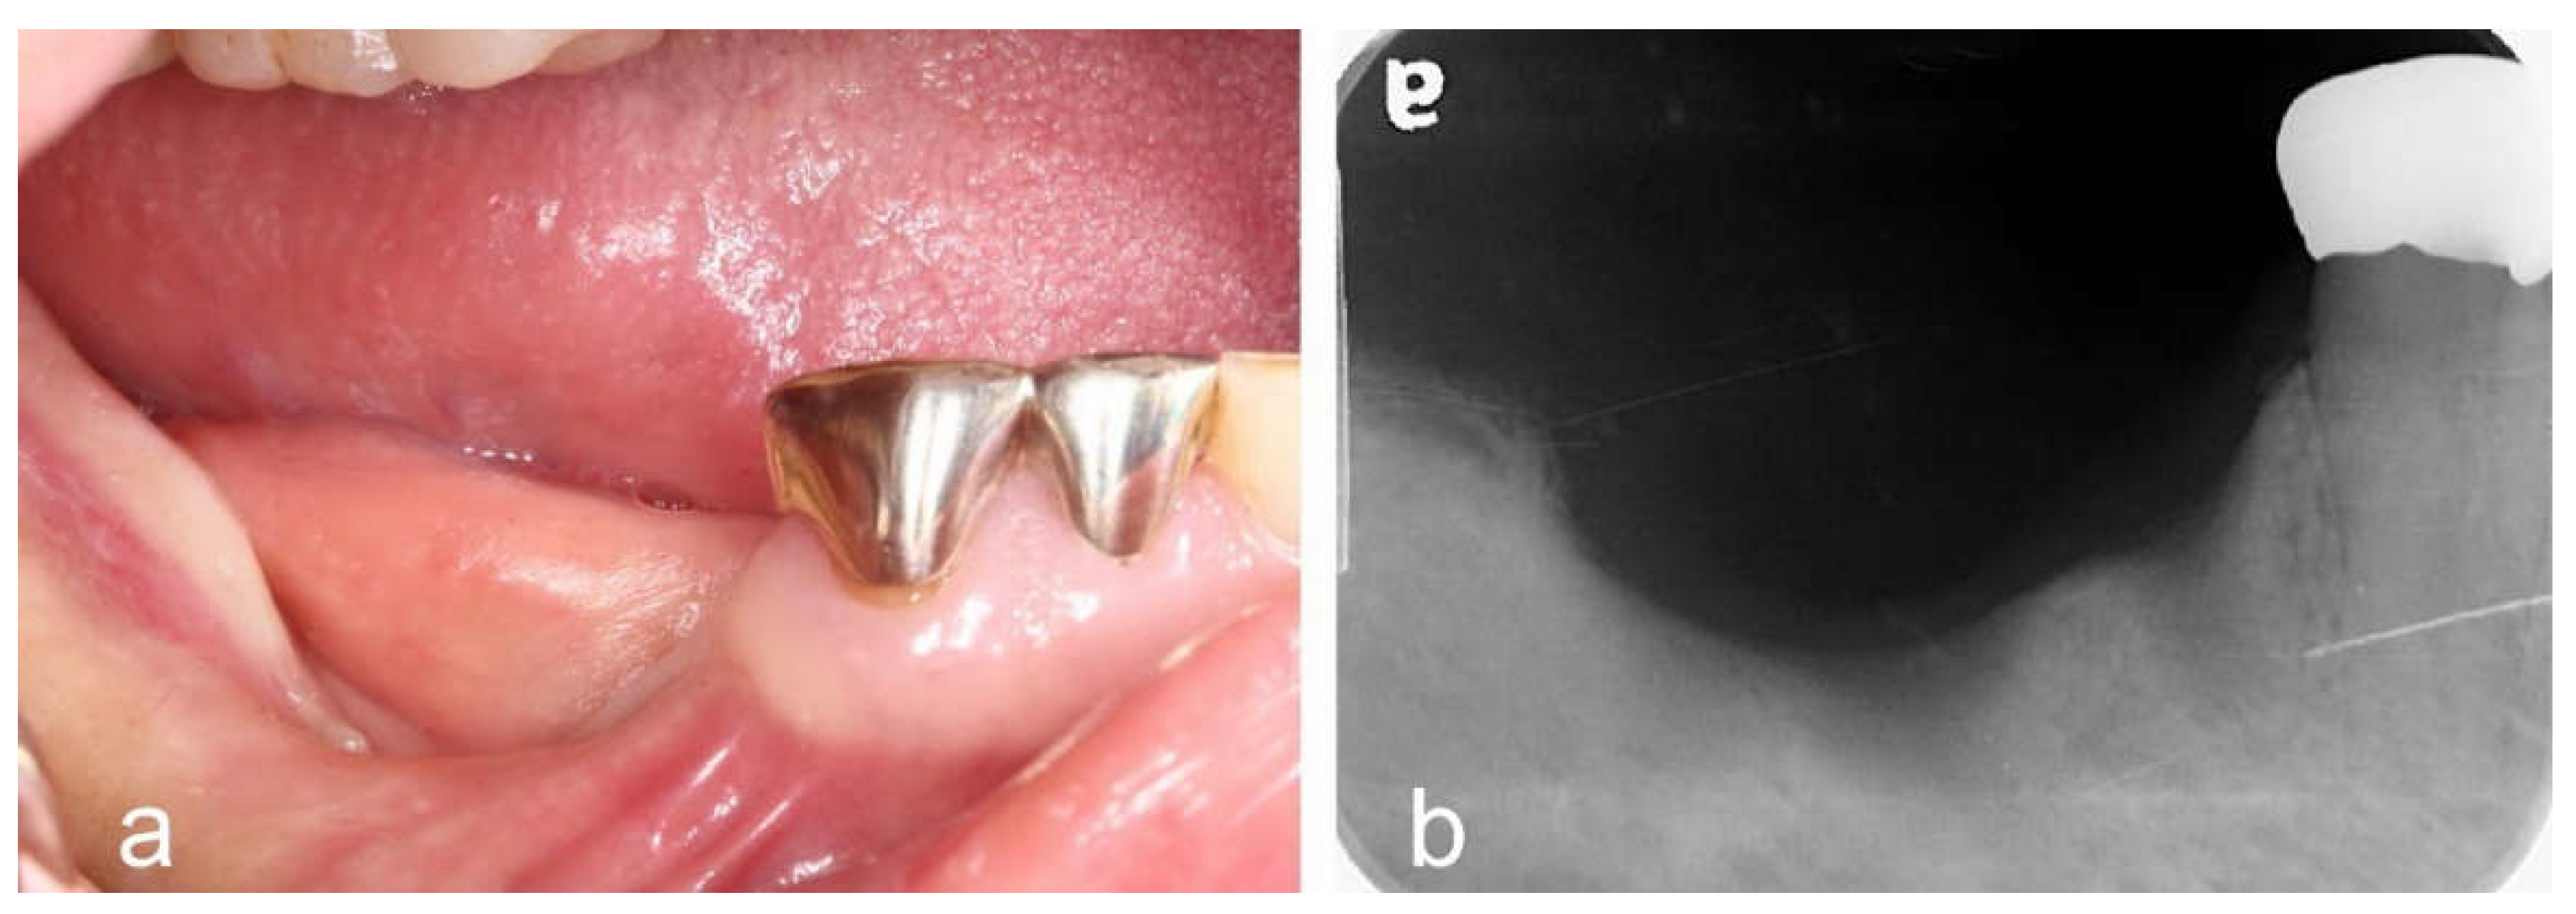

- Menchini-Fabris, G.B.; Cosola, S.; Toti, P.; Hwan Hwang, M.; Crespi, R.; Covani, U. Immediate Implant and Customized Healing Abutment for a Periodontally Compromised Socket: 1-Year Follow-Up Retrospective Evaluation. J Clin Med. 2023, 12, 2783. [Google Scholar] [CrossRef] [PubMed] [PubMed Central]